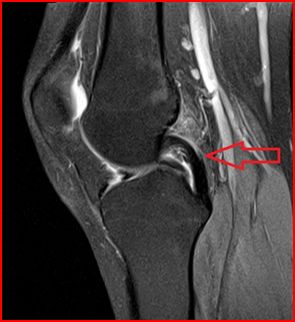

Sports Injuries: The Role Of Imaging In Diagnosis And Treatment

Sports injury imaging Page 4 Fundraising for Bowel Cancer UK Injuries of the knee are best imaged by MRI, ligaments and tendons around the joint in precise detail. Acute injuries which may be shown include meniscal tears and ligament rupture; ... Read Document